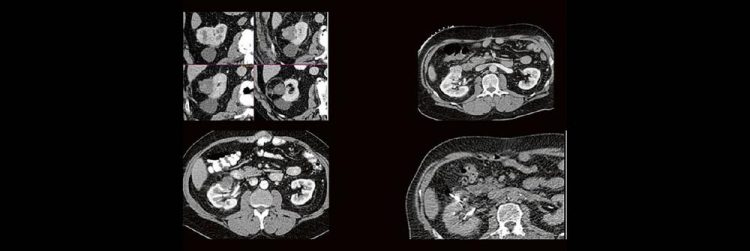

Thermoablation von Nierentumoren (Webinar | Online)

Dr. med. Sascha Alexander Pietruschka Die Anwendung von ablativen Verfahren hat sich in der klinischen Praxis etabliert. Nierentumoren bieten sich für den Einsatz von RFA und Mikrowelle an. Im Dietrich Bonhoeffer Klinikum Neubrandenburg blicken wir auf 15 Jahre Erfahrung mit mehr als 100 RFA/Mikrowellenablationen von Nierentumoren zurück. Im Vortrag werden die eigenen Erfahrungen und Ergebnisse…Continue reading Thermoablation von Nierentumoren (Webinar | Online)